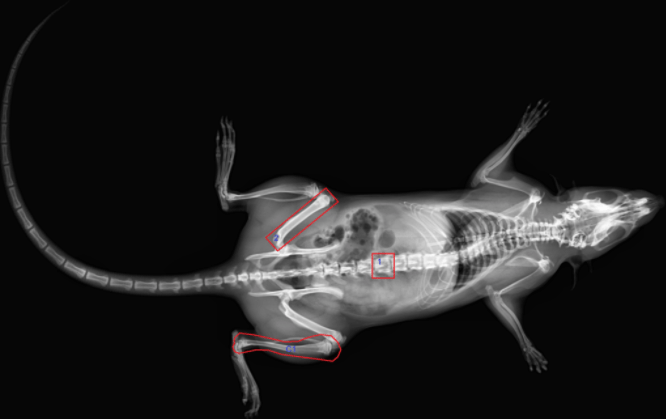

The InAlyzer DEXA scan can analyze bone mineral density (BMD) and body composition (BMC, FAT, LEAN) of live lab animals in units of 0.001gm with simple anesthesia and without dissection. Serial assessment is possible for each live lab animal, saving animals and cost. Radiation exposure of researchers is blocked with internal protection, making the InAlyzer safe, effective, and accurate for use in the preclinical research phase.

High resolution images

The InAlyzer provides high-resolution images of 5.0 lp/mm, enabling structural analysis as well as providing various images, such as bone and body composition images, for easy analysis.